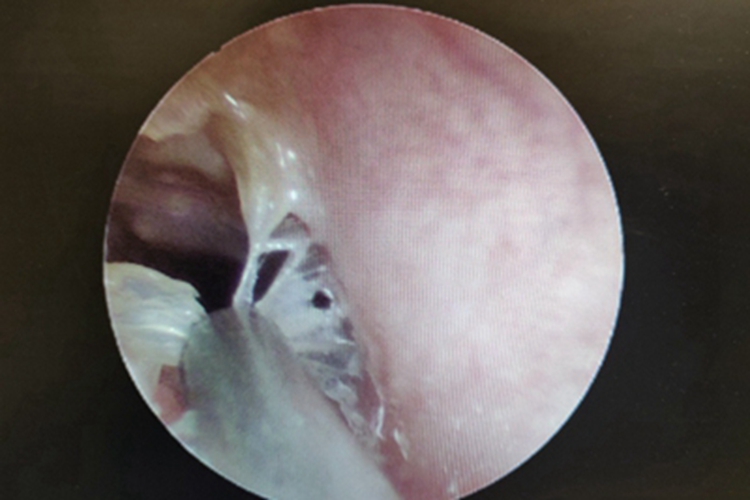

霉菌性外耳道炎的损害可发生在外耳道,其临床可表现为患者的外耳道处有大量黄白色脓液性分泌物,团块状附着于外耳道壁上,边缘有碎纸样白色鳞屑,耳朵内部黏液呈灰黑色,伴瘙痒感,以夜间为甚。